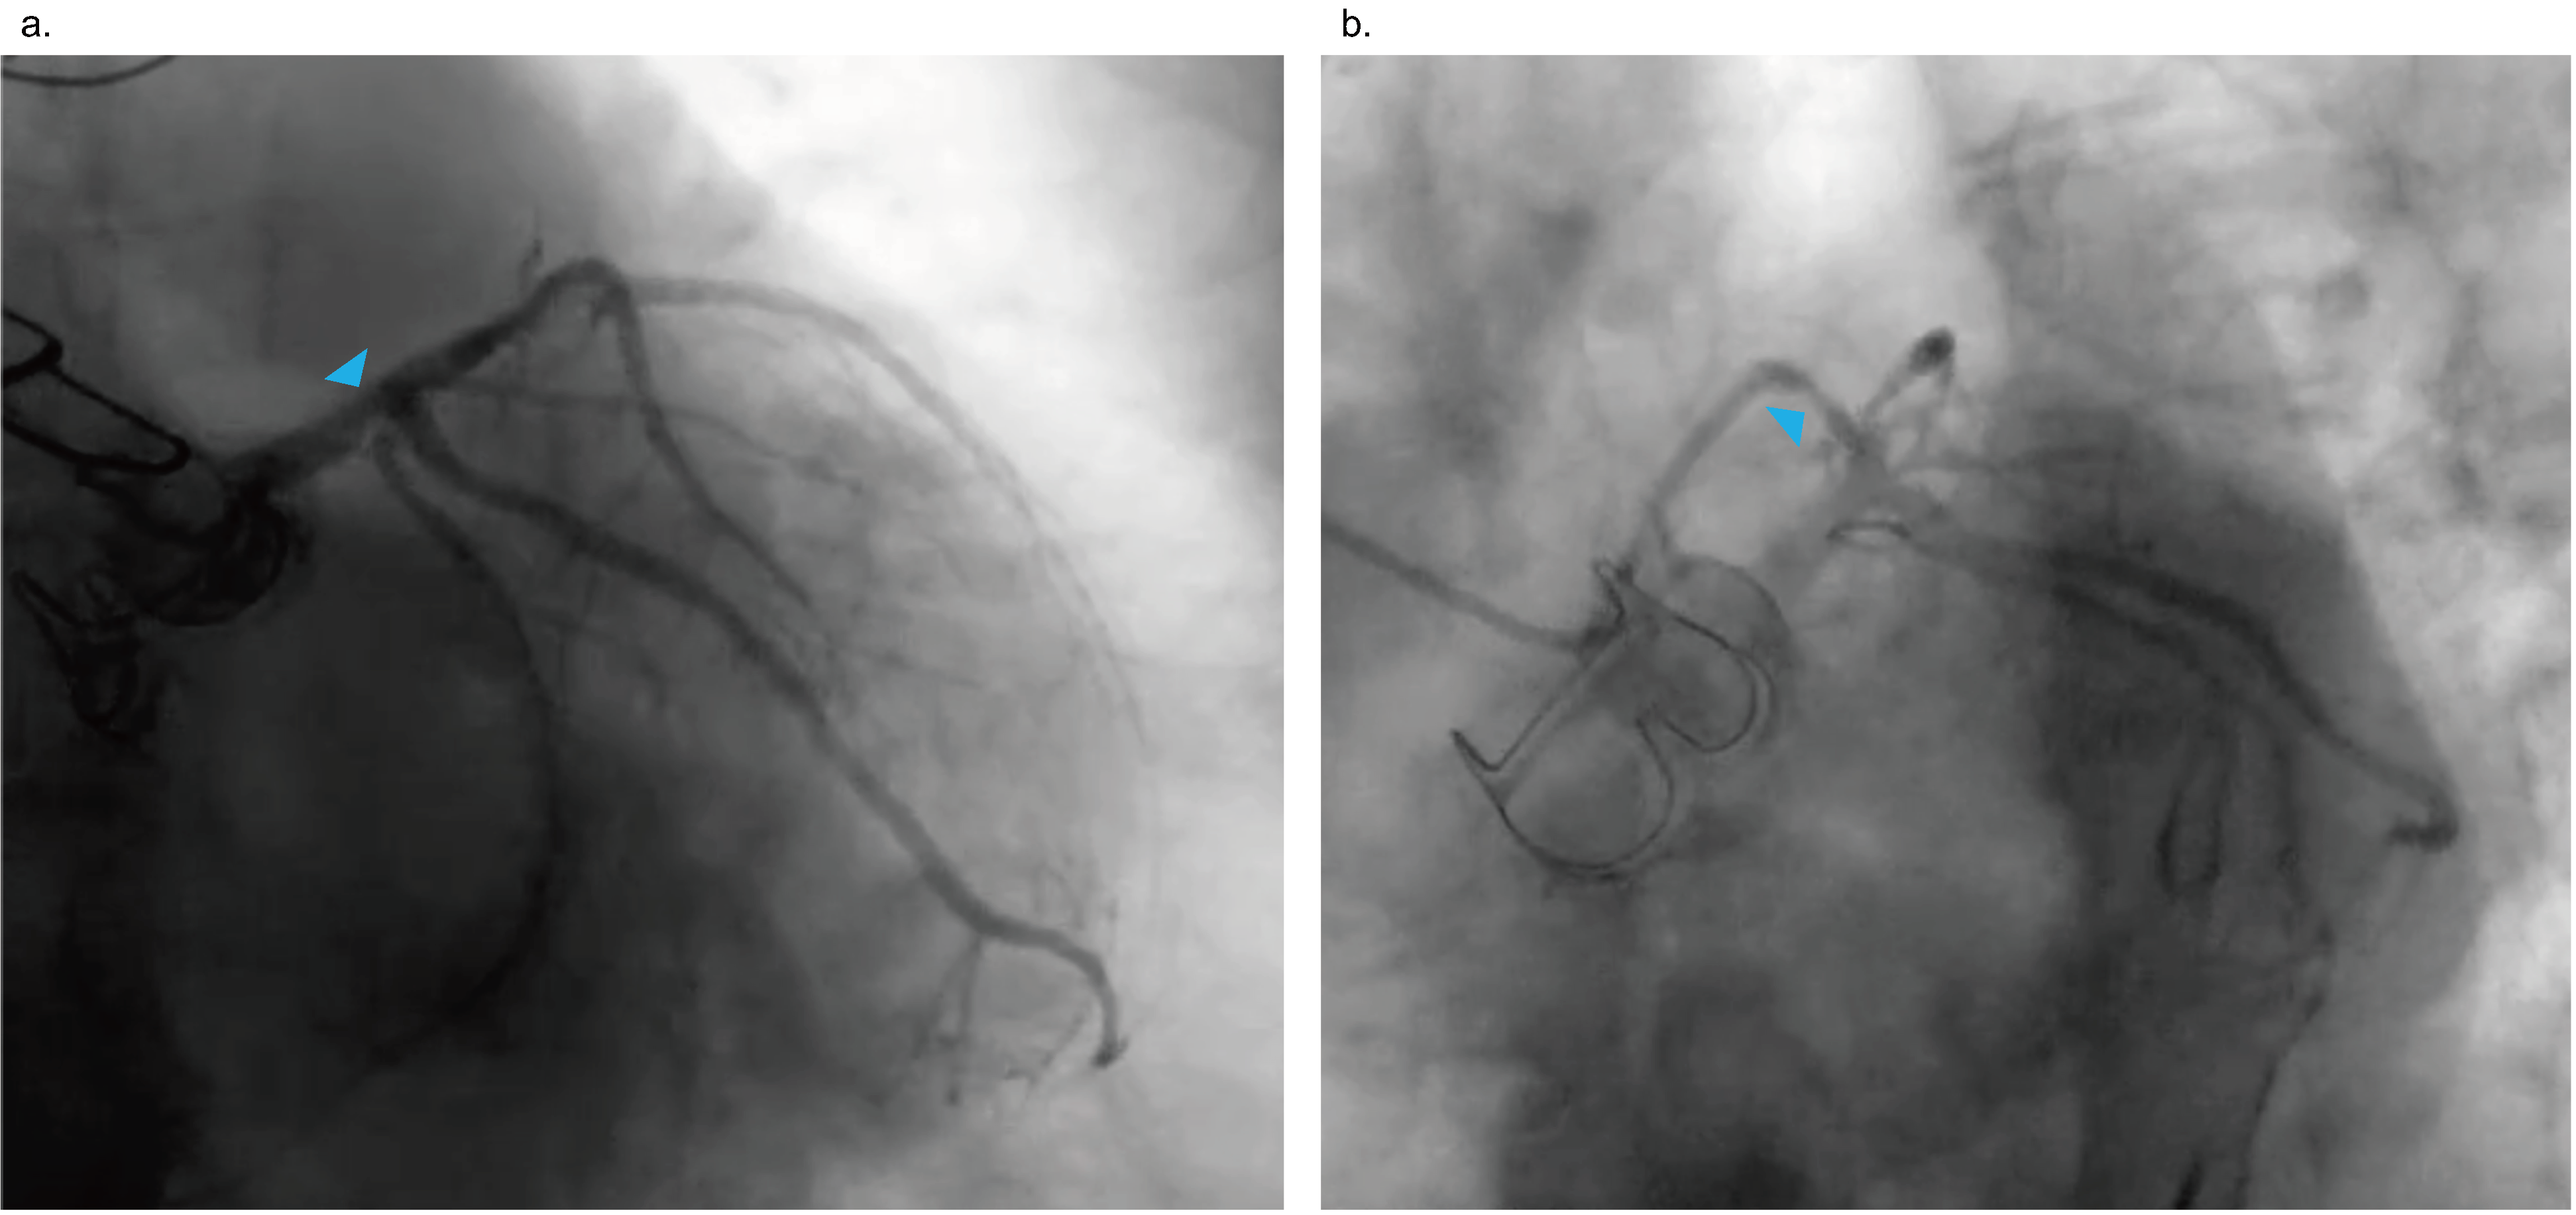

Baseline characteristics of the 10 patients are summarized in Table 1. Eight patients were octogenarians, and the other 2 patients were selected for the hybrid procedure due to their intermediate to high surgical risks. Five patients had LMCA disease, including 3 with multivessel disease. In addition, 5 patients had proximal LAD disease, 2 of whom had multivessel disease. The SYNTAX scores ranged from 13 to 35.5, and 5 patients had a SYNTAX score greater than 22 (Table 2). The Figure shows the coronary angiography of a patient with LMCA bifurcation and LAD disease (case 7). Table 2 summarizes coronary revascularization characteristics of the patients.